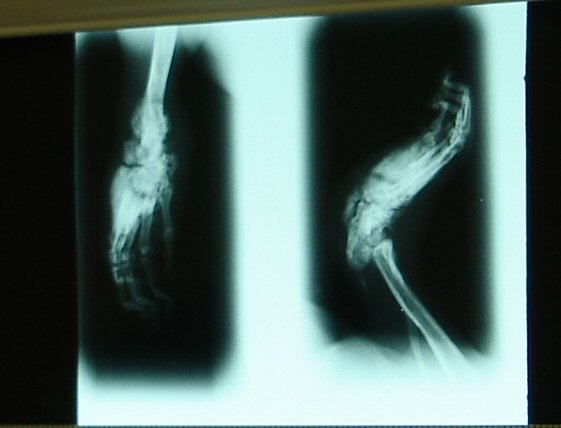

Knochenauflösung im fortgeschrittenen Stadium

Die Infektion kann sich in fortgeschrittenen Fällen der Pododermatitis auf Sehnen und Knochen ausdehnen, röntgenologisch lassen sich periostale Reaktionen,

Destruktion des Knochens bzw. eine Oseomyelitis darstellen.